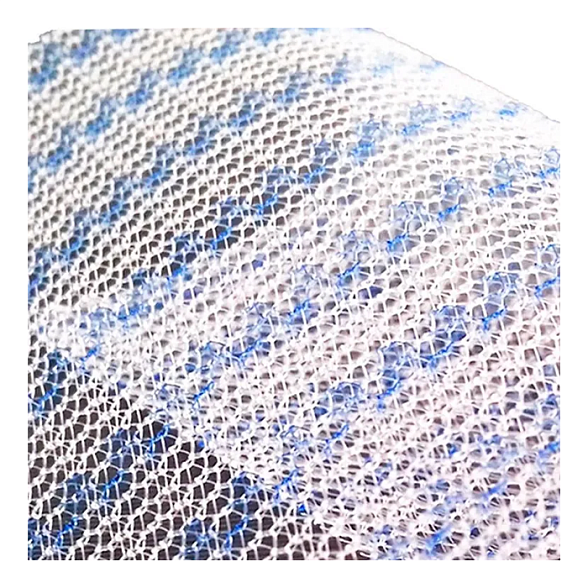

Эндопротез-сетка ЭСФИЛ — это современный, высококачественный хирургический имплантат, предназначенный для восстановительной и пластической хирургии. Изделие производится из инертного медицинского полипропилена, что обеспечивает его биосовместимость и надежную интеграцию в ткани организма. Сетка стандартного размера 30х30 см является универсальным решением для широкого спектра оперативных вмешательств, где требуется укрепление или замещение мягких тканей.

Ключевым преимуществом сетки ЭСФИЛ от «Линтекс» является ее макропористая структура. Это позволяет тканям пациента свободно прорастать через ячейки имплантата, формируя прочный соединительнотканный каркас и минимизируя риск осложнений, таких как отторжение или хроническая боль.

- Отличная интеграция: Макропористая структура способствует быстрому и полноценному прорастанию соединительной ткани, надежно фиксируя имплантат.

| Структура | Макропористая, монофиламентная или мультифиламентная (уточняется у производителя для конкретной модификации) |